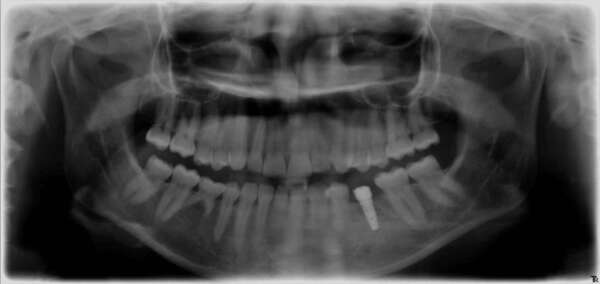

Extraction- Implantation – Mise en charge immédiate

Implants multiples : remplacement de plusieurs racines manquantes

Une dent (racines) manquante remplacée par un implant

Diaporama illustrant les étapes de la pose chirurgicale de deux implants dentaires à Paris.